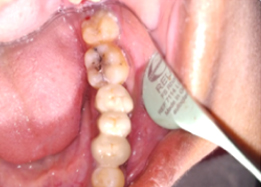

Post-OP Clinical View

PRE OP Clinical Photograph Measuring Probing Depth